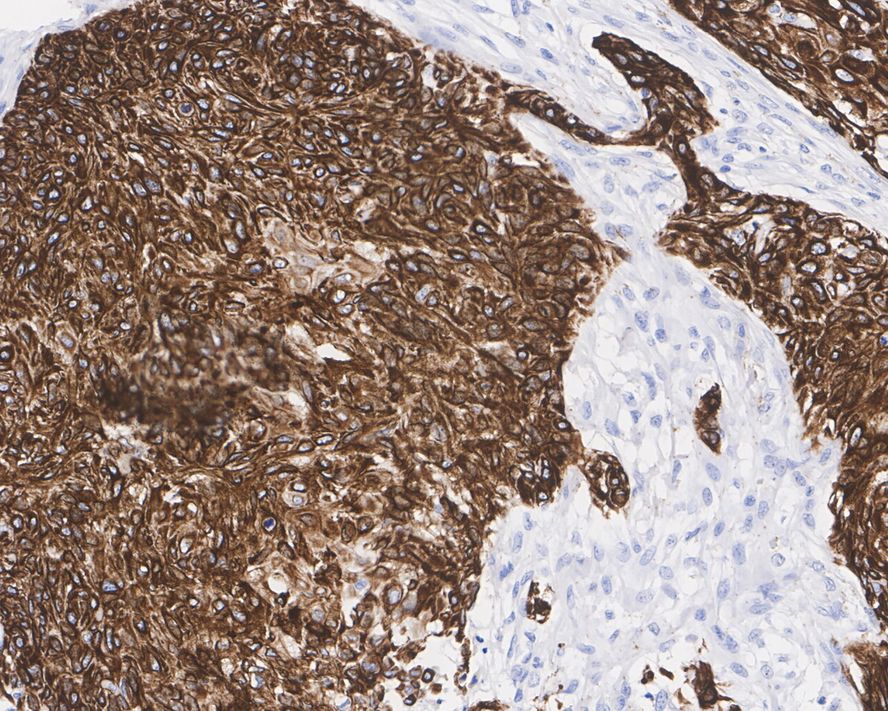

Cytokeratin 17 Recombinant Mouse Monoclonal Antibody [A2B10-R]

IHC-P

Human